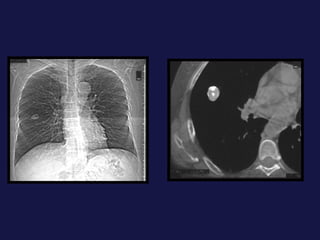

Carcinoma epidermoide ( 30% ). Bronquios centrales, ayuda la citología de esputo. Localización central. Provoca obstrucción bronquial con atelectasia o neumonía postobstructiva sin perdida de volumen mucha cavitación con paredes gruesas e irregulares. 40% lesión periférica,   con bordes espiculados o lobulados. Causa frecuente de pancoast-Tobías.

Tumor central. 60-75% próximos a los hilios. Epidermoides y células pequeñas. Agrandamiento asimétrico del hilio o masa de bordes espiculados. Atelectasia lobular, segmentaria o de todo el pulmón. Sobreinfección del parénquima distal y neumonía postobstructiva, a menudo abscesificada.

Carcinoma epidermoide (30% ). Bronquios centrales, ayuda la citología de esputo. Localización central. Provoca obstrucción bronquial con atelectasia o neumonía postobstructiva sin perdida de volumen mucha cavitación con paredes gruesas e irregulares. 40% lesión periférica, con bordes espiculados o lobulados. Causa frecuente de pancoast-Tobías.

Tumor central. 60-75%próximos a los hilios. Epidermoides y células pequeñas. Agrandamiento asimétrico del hilio o masa de bordes espiculados. Atelectasia lobular, segmentaria o de todo el pulmón. Sobreinfección del parénquima distal y neumonía postobstructiva, a menudo abscesificada.